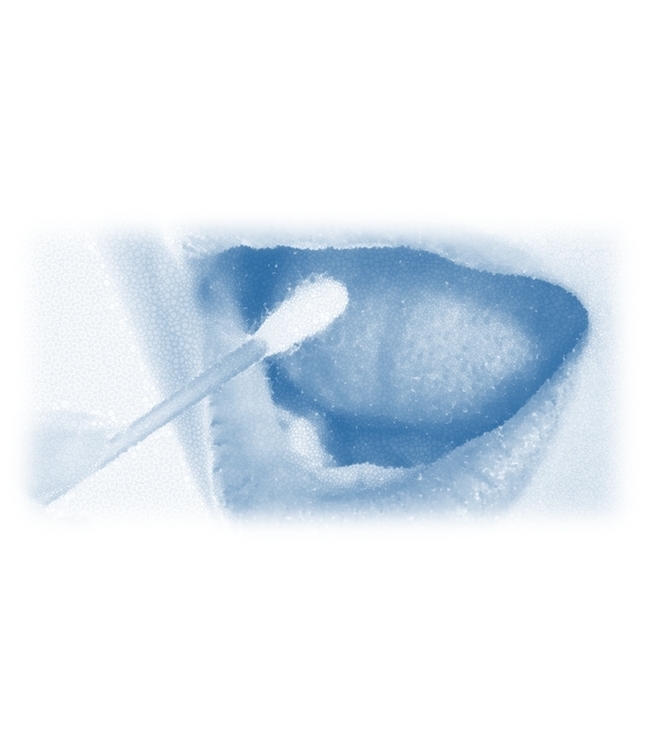

- test HPV cavo orale autoprelievo

test HPV cavo orale autoprelievo

Scopri la presenza di infezione del cavo orale da virus HPV ad alto/medio rischio, nella donna e nell'uomo.